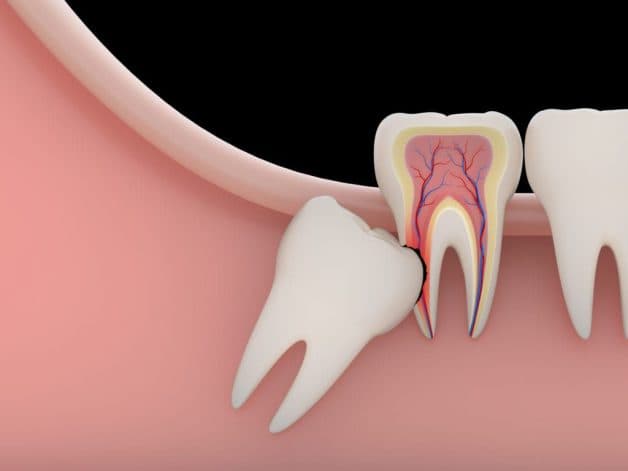

Răng khôn gây ảnh hưởng lớn đến những răng bên cạnh, khiến các răng lung lay, tiêu xương và có nguy cơ bị mất răng

Như đã nói ở trên, răng khôn mọc lên khi cung hàm đã đủ răng chính vì vậy thường xảy ra hiện tượng răng mọc chen chúc hay mọc lệch đâm sang những răng bên cạnh. Đây chính là nguyên nhân chính khiến cho các răng khác bị lung lay, tiêu xương hoặc thậm chí là mất răng.